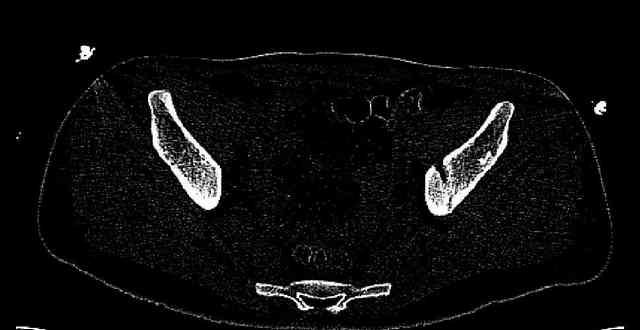

While not claiming to have the best 3D brain around, it appears to me from the limited images available, that the caudal segment is stable from the symphysis to the SI joint on the fracture side. I would love to see the rest of the transverse CT images to see where the fracture line actually exits posteriorly on both the inner and outer tables of the ilium. In my hands,

Some more images. Does it help to guess which part of the acetabulum is displaced?

Normal appearing SI joints and a healed posterior column limb... my bet's on caudal segment displacement.